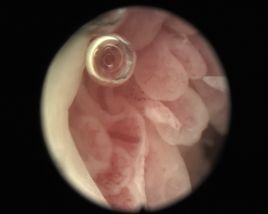

血管翳。血管翳不但隔絕了骨頭通過滑膜獲取營養,而且能釋放多種炎性介質與蛋白水解酶等,對關節軟骨、軟骨下骨、韌帶肌腱等組織進行侵蝕,引致骨關節軟骨破壞,軟骨下骨溶解,關節囊破壞鬆弛,關節錯位,關節融合,以致骨化。血管翳:是由漿細胞、巨噬細胞、及淋巴細胞共同形成,釋放免疫球蛋白與RF的能力。可見於強直性脊柱炎(AS),類風濕性關節炎。